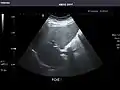

Kidneys: Right and left kidneys measure 11.5 cm and 12 cm in length respectively. No hydronephrosis. Small left lower pole kidney cyst.

Right kidney

Left kidney